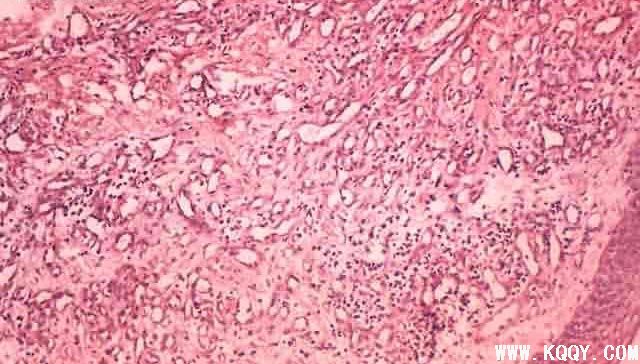

牙龈瘤组织图片

牙龈瘤

组织

图片